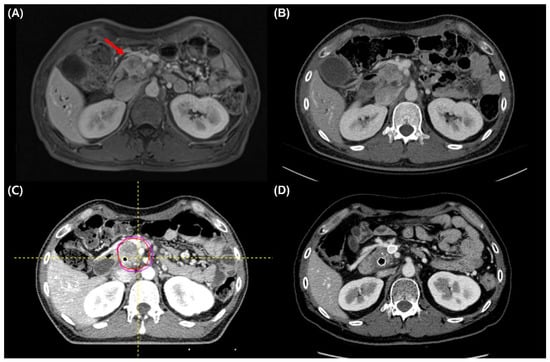

2.2. Treatment